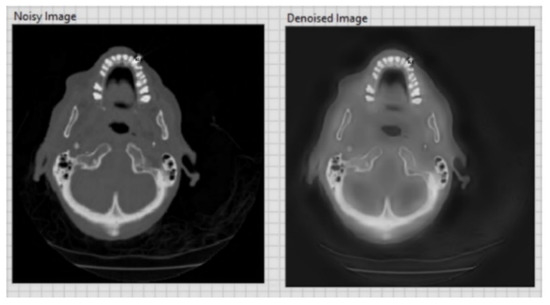

| CT image (Figure 9) 256 × 256 | 26.09 | 0.05 |

| CT image (Figure 10) 256 × 256 | 20.18 | 0.1 |